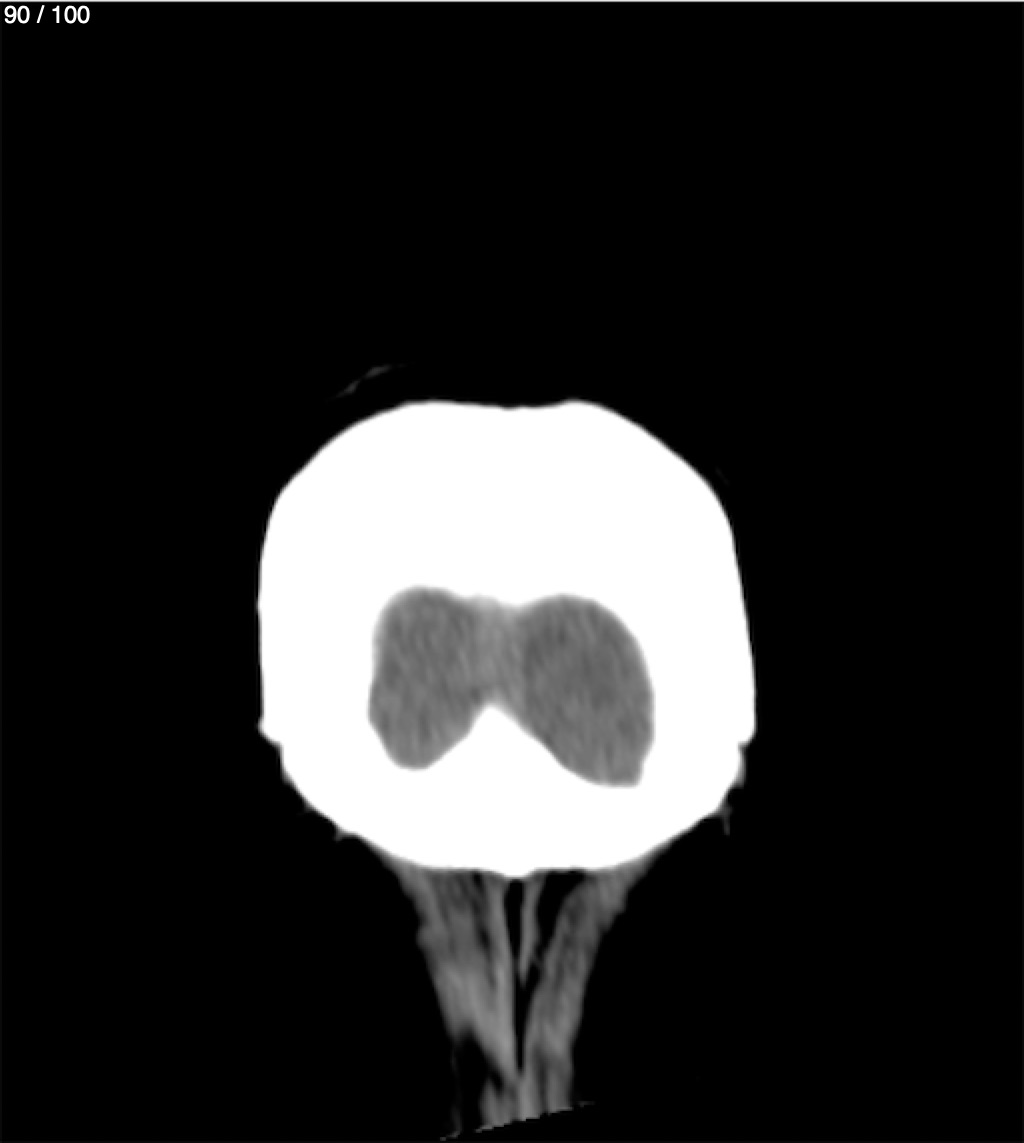

Jose Sosa Martinez 66A - Angiotac Craneo